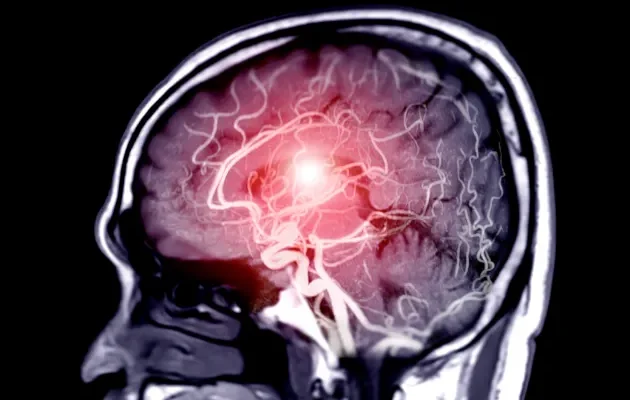

Anevrizma, arterlerin (kan damarlarının) duvarlarında oluşan anormal genişlemelerdir. Bu genişlemeler, damar duvarının zayıf bir bölgesinde meydana gelir ve zamanla balon gibi şişebilir. Anevrizmalar genellikle beyin arterlerinde (serebral anevrizma) veya aortta (aort anevrizması) oluşur, ancak vücudun herhangi bir yerindeki arterlerde gelişebilirler.

Beyin MR‘ı, beyindeki ve çevresindeki damarlarda anevrizma olup olmadığını kontrol etmek için kullanılır. Özellikle beyin anevrizmalarının tespitinde etkilidir.

Güçlü manyetik alanlar ve radyo dalgaları kullanarak beyin ve damarlarının detaylı görüntülerini sağlar. Bazen anevrizmanın daha net görülmesi için kontrast madde kullanılabilir.